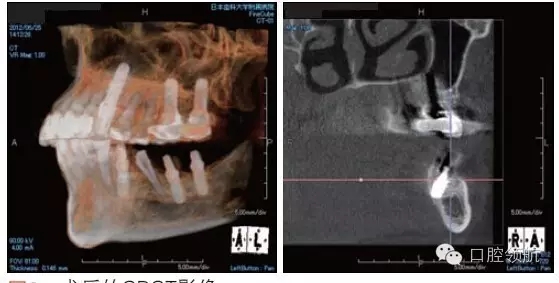

利用曲面斷層及CBCT檢查埋入部位情況,雖未出現(xiàn)與主訴相關(guān)的神經(jīng)損傷,但無意中卻發(fā)現(xiàn)了種植體的舌側(cè)穿孔(圖1、圖2)。

圖2 術(shù)后的CBCT影像。

雖不能確定是裂鉆備洞還是植入種植體所造成的穿孔,但從4個(gè)月的病情的發(fā)展看,考慮可能是術(shù)中的舌下動(dòng)脈損傷導(dǎo)致口底軟組織內(nèi)出血而造成的感覺異常。采用常規(guī)藥物及物理療法開始進(jìn)行治療。